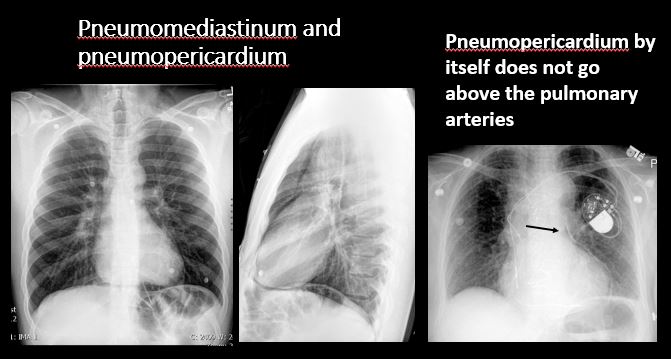

Section 1 Submit Findings Case322 Findings Technique The exam is expiratory, rotated, over or under penetrated, or limited by overlying structures or soft tissues, body habitus, patient positioning, or motion. Yes No Support Devices There is a vascular line or lines present in an abnormal location or otherwise abnormal. Yes No There are other devices such as a chest tube or pleural drain, feeding, NG, or gastrostomy tube, LVAD or pacemaker, vascular stents, cardiac valves, anesthesia catheter, VP shunt, neurostimulator, or other drains or tubes present that are in an abnormal position or are otherwise abnormal. Yes No Cardiomediastinum The superior mediastinum is abnormally widened considering the technique. Yes No There is abnormal shift of the mediastinum. Yes No There is a mass or other abnormal density in or overlying the mediastinum. Yes No There is an abnormality in the retrosternal, retrotracheal, or retrocardiac space on the lateral view. Yes No There is abnormal tracheal deviation or narrowing on the frontal and/or lateral view. Yes No There is pneumomediastinum and/or pneumopericardium. Yes No There is enlargement of the cardiac silhouette. Yes No The heart borders are abnormal. Yes No The right paratracheal stripe is thickened or enlarged. Yes No The azygoesophageal recess is displaced or otherwise obscured. Yes No Vasculature and Hila The aorta is dilated, tortuous, ectatic, calcified, or there is a focal contour abnormality. Yes No The central pulmonary arteries or hila are enlarged. Yes No The aorto-pulmonary window is convex or obscured by a mass, adenopathy, or vasculature. Yes No There is cephalization or haziness of the pulmonary vessels or congestion of the central pulmonary vasculature. Yes No Lungs The lungs are hyperinflated or underinflated generally or segmentally. Yes No There is focal, multifocal, or diffuse airspace disease, mass, opacity, or nodularity. Yes No There is focal or diffuse interstitial disease. Yes No There is focal or lobar atelectasis or total collapse of the lung. Yes No There is cavitary or cystic disease with or without air fluid levels or soft tissue nodularity. Yes No The position of the major and minor fissures is abnormal. Yes No The right or left hemidiaphragm is focally or diffusely obscured on the frontal and/or lateral view. Yes No There is elevation, depression, or contour abnormality of the right or left hemidiaphragm. Yes No Pleura There is focal or diffuse abnormality of the pleura or chest wall. Yes No There is a pleural effusion, blunting of the costophrenic angle, or posterior sulci. Yes No There is focal fluid in the fissures. Yes No There is asymmetric pleural thickening or capping of the apices. Yes No There is a pneumothorax, hydro/pneumothorax, or hemo/pneumothorax. Yes No Bones, Soft Tissues, Upper Abdomen The ribs, clavicles, shoulder, spine, or other visualized bones are abnormal. Yes No There is free air beneath the diaphragm. Yes No The bowel or organs of the upper abdomen are abnormal. Yes No There is subcutaneous emphysema, focal or diffuse soft tissue abnormality, radiopaque foreign body, or post-surgical change or hardware. Yes No